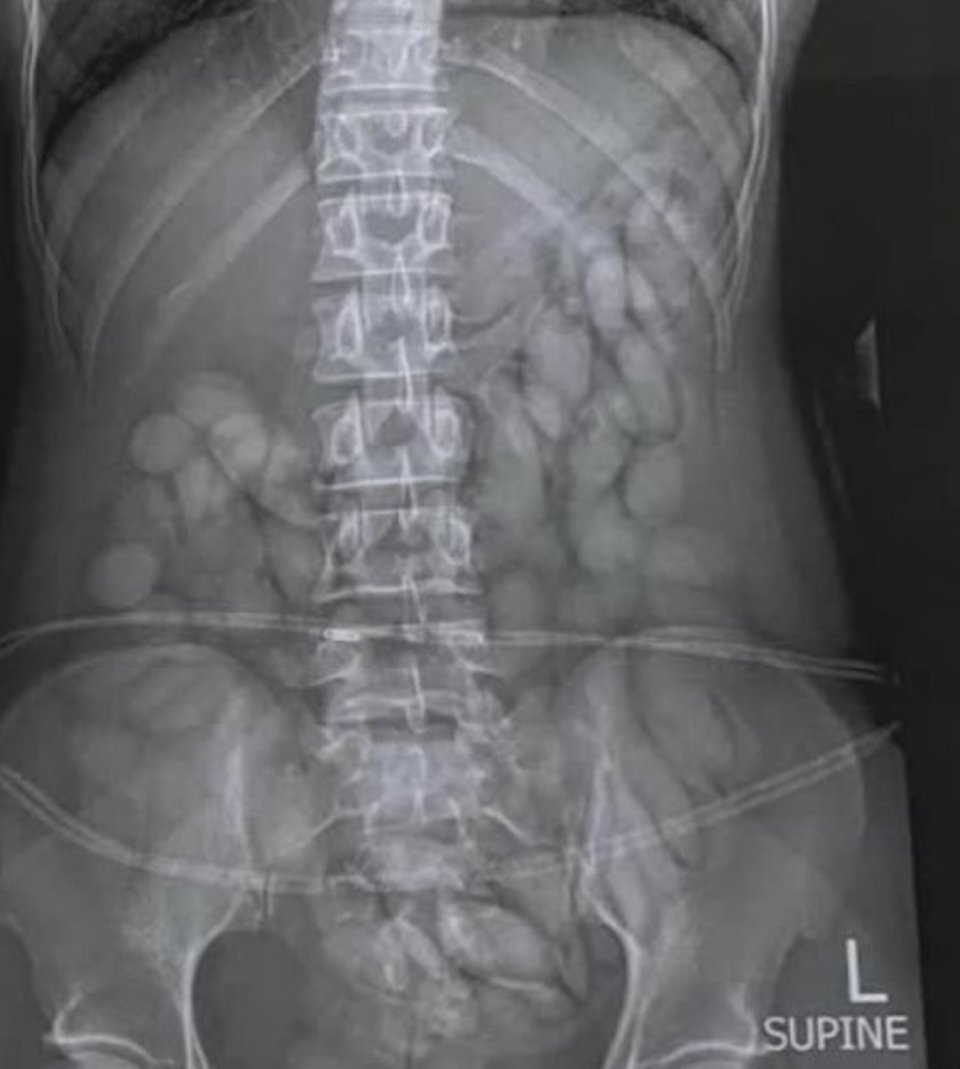

Μια γυναίκα που συνελήφθη σε ένα από τα πιο πολυσύχναστα αεροδρόμια της Νότιας Αφρικής κατηγορήθηκε για διακίνηση ναρκωτικών, αφού ακτινογραφίες αποκάλυψαν στο στομάχι της δεκάδες σφαιρίδια που η αστυνομία θεωρεί ότι περιέχουν κοκαΐνη, μετέδωσε το SkyNews.

68 αμπούλες κοκαΐνης βρέθηκαν στο στομάχι της

Μετά τη σύλληψή της, η γυναίκα μεταφέρθηκε σε τοπικό νοσοκομείο, όπου η ακτινογραφία αποκάλυψε τα αντικείμενα στο στομάχι της, που φαίνεται ότι είχε καταπιεί, τα οποία στη συνέχεια αφαιρέθηκαν.